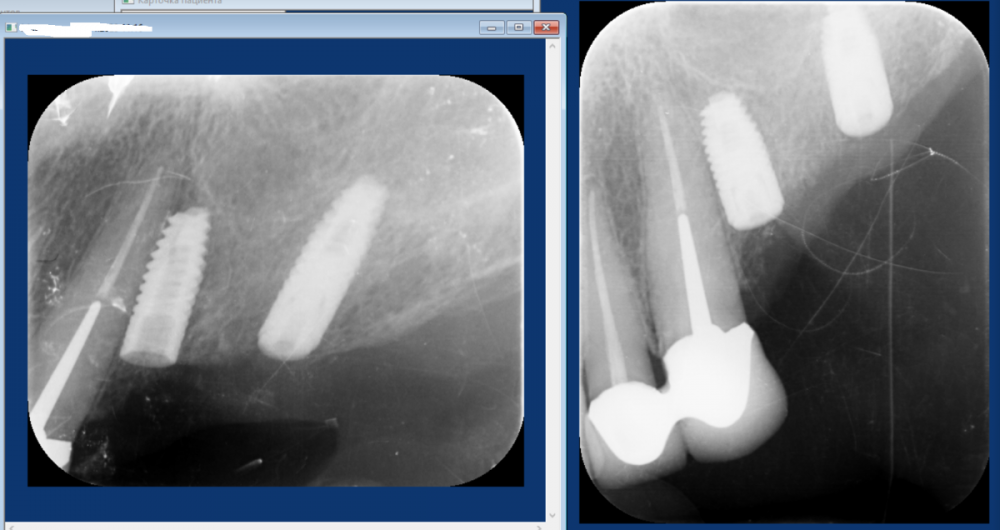

Dr T Опубликовано 13 мая, 2023 Поделиться Опубликовано 13 мая, 2023 (изменено) Уважаемые стоматологи, прокомментируйте, пожалуйста, что можно порекомендовать в данной ситуации доктору нашей клиники. Предполагался мост на имплантатах зубы 24-26, мужчина, 45 лет. Доктор выбрал 2 имплантата 4.2 по 8мм. Кость по КТ хорошая, но в ходе имплантации что-то пошло не так. В конечном итоге, один имплантат стал близко к зубу и то со второго раза и подсыпалась косточка. Можно ли оставлять как есть или слишком близко к зубу и что делать? Имплантация была 2 недели назад. На снимках первая установка и потом после попытки выпрямить 24 имплантат. Изменено 13 мая, 2023 пользователем Dr T Ссылка на комментарий

Dr T Опубликовано 13 мая, 2023 Автор Поделиться Опубликовано 13 мая, 2023 @Женька Да, без позиционера. Первый из последних двух снимков был сделан в день имплантации, а последний - через 2 недели. Ссылка на комментарий

Aquarius Опубликовано 14 мая, 2023 Поделиться Опубликовано 14 мая, 2023 Ощущение, что хит-рут имеется. Следы витков на корне. Могу ошибаться( Ссылка на комментарий